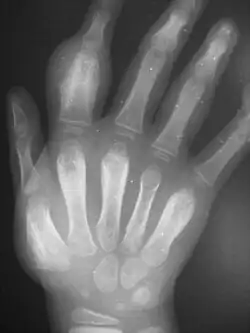

Secondary yaws affects the skin and bones.[12] The most common bone-related problem is periostitis, an inflammation around the bone, which often occurs in the bones of the fingers and the long bones of the lower arms and legs, causing swollen fingers and limbs.[12] This causes pain at night and thickening of the affected bones (periostitis).[2] About 75% of infected children surveyed in Papua New Guinea reported joint pain.[2] Swollen lymph nodes, fever, and malaise are also common.[12]

Tertiary yaws can include gummatous nodules. It most commonly affects the skin. The skin of the palms and soles may thicken (hyperkeratosis). Nodules ulcerating near joints can cause tissue death. Periostitis can be much more severe. The shinbones may become bowed (saber shin)[12] from chronic periostitis.[2]